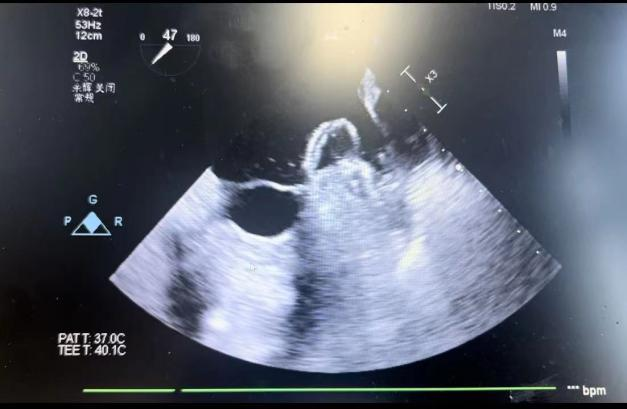

在食道超声引导下进行房间隔穿刺,由于心耳为反鸡翅型,穿刺位点需靠下靠前,潘教授先在90度双腔切面将定位靠下,再在45度主动脉短轴切面将定位靠前。穿刺成功后上导丝交换先健LAnavi™分段控弯导引系统送至心耳口部,经过A、B双弯的调整使得鞘管轴向与心耳同轴,获得理想封堵位置。然后推送钢缆释放出固定盘,锚定后退鞘释放出封堵盘。超声下观察贴合良好,无明显残余分流,牵拉测试稳定,即释放左心耳封堵器。释放后再次通过超声各个角度进行验证,封堵结果完美有效,整个过程一气呵成,手术取得了极大的成功。

牵拉测试稳定 完美有效封堵